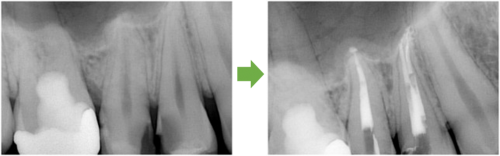

抜髄 奥歯の神経の治療 川口の歯科 歯医者 さかえ歯科クリニック

2014年12月15日